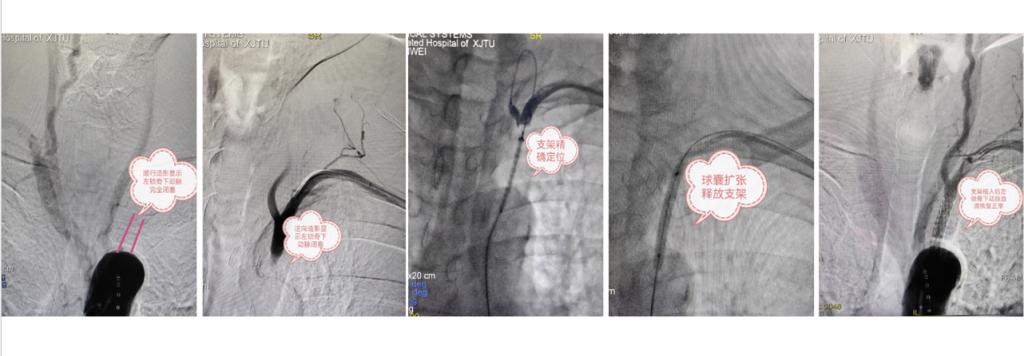

几天后,铜川市85岁高龄的李先生也因相似的症状慕名来心血管外科就医。经相里伟医生仔细检查评估后也确诊为左锁骨下动脉盗血综合征并安排手术治疗。术中造影后发现李先生的病变程度更严重,左锁骨下动脉完全闭塞,经股动脉顺行通路反复尝试难以开通闭塞段动脉,在李万静医生协助下改行经桡动脉穿刺通路最终成功逆向开通闭塞血管,顺利植入LifeStream支架恢复左锁骨下动脉正常血流(图2)。术后头晕手麻的症状显著改善,两天后李先生和家人满意的出院回家。

图2